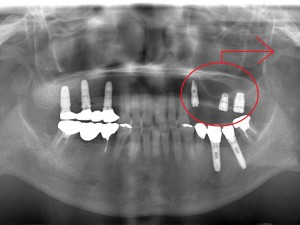

60代 男性 インプラント症例

60代 女性 S様

上下入れ歯の患者様です。入れ歯に違和感があったため来院されました。

右上3本、左上3本、左下2本のインプラントを埋入。

右上は骨が足りない為サイナスリフトをしてインプラント手術を行いました。

術後のレントゲン写真